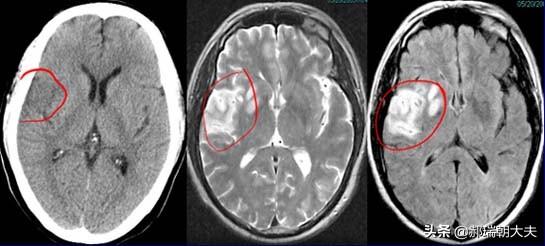

- Toutefois, outre les différences de présentation clinique, il arrive parfois que l'on ne soit pas en mesure d'évaluer l'efficacité du traitement.Le diagnostic ne peut pas être établi uniquement sur la base des symptômes cliniques.Les résultats doivent également être obtenus à l'aide de tests d'imagerie, tels queCT crânien et IRM crânienne. Qu'il s'agisse d'un infarctus lacunaire ou d'un infarctus cérébral, il n'y a pas de changement significatif au scanner crânien dans les 24 heures car le tissu cérébral est seulement ischémique et hypoxique, et il n'y a pas de nécrose liquéfiée du tissu cérébral infarci. Il est possible de l'identifier dans une certaine mesure lorsqu'il date de moins de 24 heures. Dans la phase aiguë des symptômes, l'IRM crânienne est le premier choix d'examen en clinique. Il existe différentes séquences d'IRM, et différentes séquences d'IRM peuvent être utilisées pour réaliser des examens pertinents pour différents cas.Pour le diagnostic de l'infarctus cérébral, les séquences DWI peuvent être très intuitives pour clarifier la situation.。

(3) Examen : tomodensitométrie ou examen magnétique nucléaire de la tête, le meilleur étant l'examen magnétique nucléaire, qui permet de trouver des foyers caverneux dans les parties correspondantes du cerveau.

Le diagnostic d'infarctus cérébral et d'infarctus cérébral lacunaire doit être précisé par un scanner ou une IRM cérébrale, car l'hémorragie cérébrale et l'infarctus cérébral ont les mêmes manifestations et il n'est pas possible de juger sur la base des manifestations.